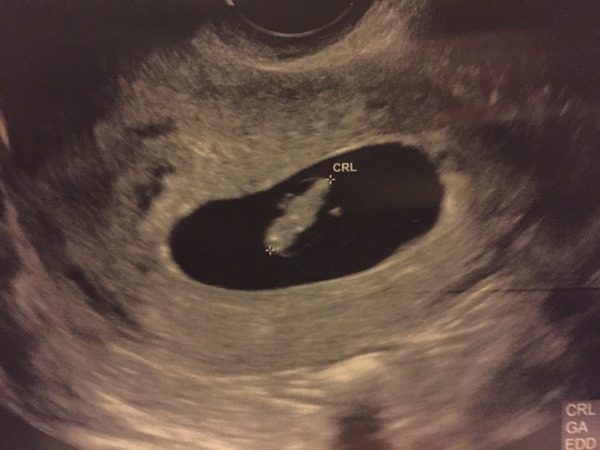

Sorry I've been awol, I'm struggling to keep up! I had some bleeding on Monday so I ended up getting seen at the emergency gynae unit...they were so lovely, and thankfully this little bean was there with a heartbeat! I've never been so relieved!

Lovely scan Elle

Laurenrl · 21/04/2016 23:35

elle Yeah here it is

Sorry you had a scare so glad everythings ok!

Thread #5 - TTC#1 grads thread - now we're cooking with charcoal!

leoniethelioness · 22/04/2016 07:33

What a cool scan, Lauren! Starting to look like a real baby!

Amazing picture Lauren!